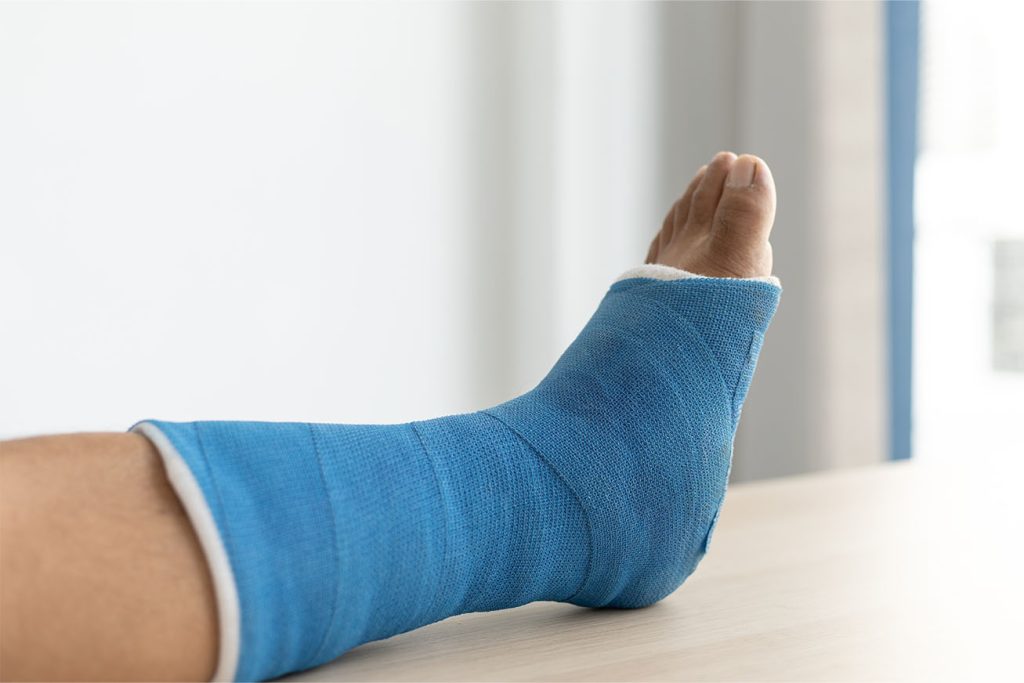

Nonsurgical treatment

If the ankle fracture is stable and the bones remain in good alignment, surgery may not be necessary. Treatment usually involves applying a plaster cast, short leg cast, or a removable boot to keep the ankle supported while it heals. Patients are typically advised to avoid putting weight on the injured leg for around six weeks, though this period may be longer if healing is slow or if other health conditions, such as diabetes, are present.